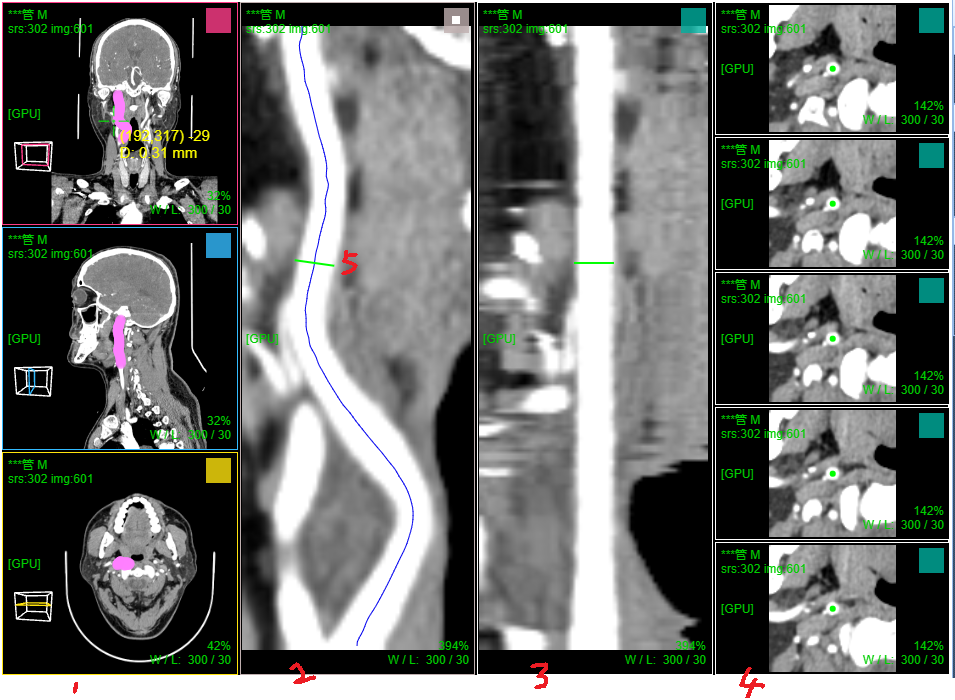

十、血管CPR曲面拉伸拉直

打开血管增强造影序列; 菜单 选择 "路径点手工标记"

在MPR切片上选取2个血管中心点,确定血管起始位置和前进方向

菜单 选择 "血管中心辅助提取"

滚轮下滚则则沿当前方向前进自动检测下一个血管中心位置和检测到的大小(图示5 圆为检测血管半径,红点为中心; 绿点为重建血管垂直切面中心)

滚轮上滚则回退并删除当前检测的血管中心点

鼠标滚轮在重建血管垂直切面右侧(图示3)上下滚动 则调整切面X轴方向以便切面和血管垂直, 在MPR上可看到该切面和血管的交线(绿线)

鼠标滚轮在重建血管垂直切面下侧(图示4)上下滚动 则调整切面Y轴方向以便切面和血管垂直, 在MPR上可看到该切面和血管的交线(绿线)

鼠标左键按下并移动则拖动改变当前检测血管中心点的位置,滚轮在检测点(红点)上滚动则调整检测的血管半径大小(仅仅确定前进步长用)

点击自动前进并检测(图示2) 则程序自动沿血管中心路径前进并检测记录中心点位置;如果检测失败则停止前进,需手工干预调整

注:自动检测前进时 还可通过包围盒裁剪设定检测截至范围

血管中心检测提取结束后,菜单 选择 "血管CPR拉直渲染"

窗口1:MPR窗口

窗口2:血管CPR拉伸; 窗口3:血管CPR拉直; 窗口4:当前血管位置(绿线)垂直重建切片和前后切片

滚轮在窗口2和窗口3上滚动可调整 当前血管位置(绿线, 图示5)

滚轮在窗口2和窗口3 右侧上下滚动 则可沿血管中心360旋转CPR

窗口2:血管CPR拉伸 支持厚切,可开启厚切